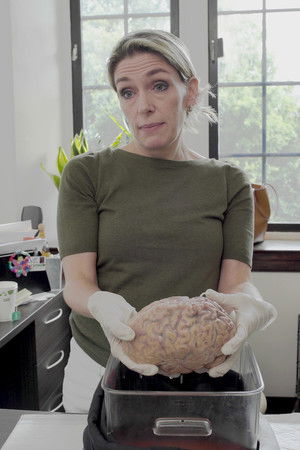

Director Penny Lane’s decision to become a “good Samaritan” by giving one of her kidneys to a stranger turns into a funny and moving personal quest to understand the nature of altruism. “Confessions of a Good Samaritan” is a provocative inquiry into the science, history, and ethics of organ transplantation, asking an ancient question in a whole new way: Who is your neighbor, and what do you owe them?